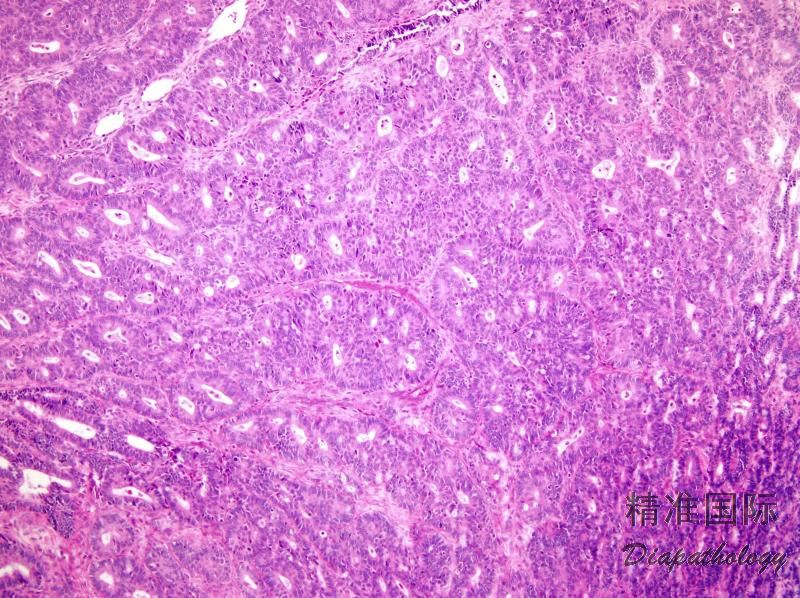

常见的癌结构是腺体增生分支、出芽、高度复杂的乳头状、腺体背靠背、腺体融合或筛状结构,范围超过 5mm;

少数病例间质中见不规则腺体、分布不均匀且边缘不规则的癌巢,周围常常伴有水肿或炎症性间质反应;边缘呈锯齿状的实性区和单个细胞的浸润;

细胞常呈复层排列,腔缘包膜清楚,有不同程度的异型性;